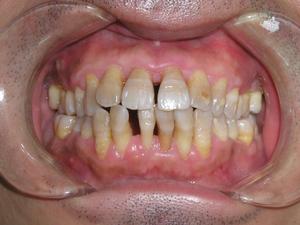

到了牙周病重期,牙槽骨几乎全部消失,牙根会露出大部分,牙齿会异常松动,甚至脱落。此时疼痛感强烈,难以咀嚼食物。

(重度牙周炎后期,牙根几乎暴露,牙齿变得异常松动)